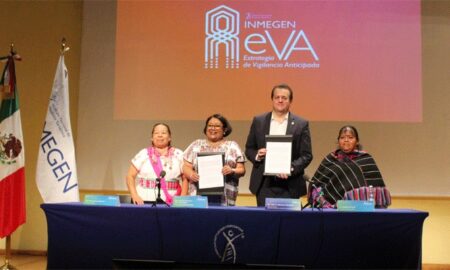

882Salud y nutriciónUna herramienta de Vigilancia Anticipada para la prevención de cáncer, presentó Inmegen

Conoce tu historia, eVAlúa tu riesgo y toma el control.